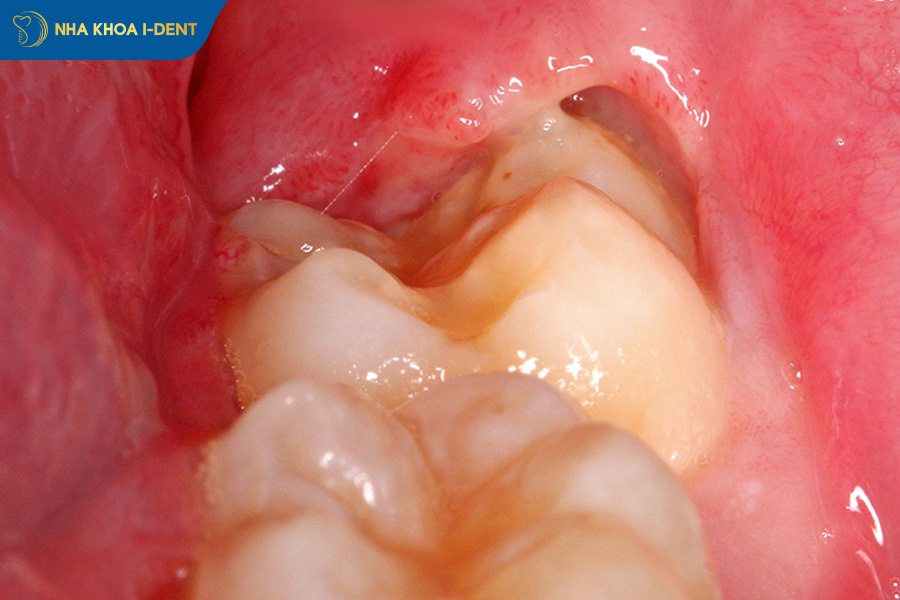

- Viêm lợi trùm: Phần lợi phía trên không rút hết, tạo thành túi lợi chứa vi khuẩn gây sưng đau, mủ và hôi miệng tái phát nhiều lần.

Trường hợp răng khôn mọc thẳng nhưng bị viêm lợi trùm cần nhổ bỏ.